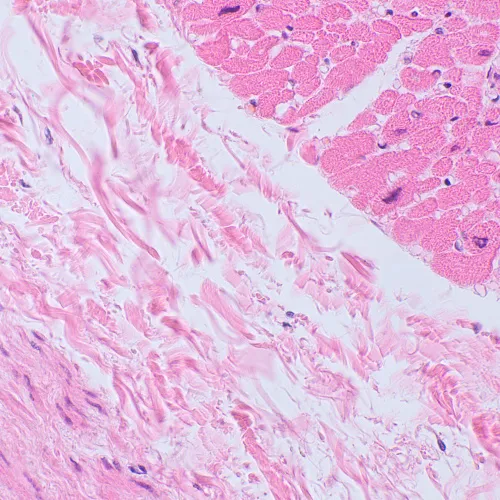

Il microscopio MAGUS Bio 250BL può essere usato per attività di laboratorio, per la ricerca scientifica e l’insegnamento. È progettato per osservare campioni in sezioni sottili e strisci di materiali biologici in luce trasmessa. Il principale metodo di osservazione è la microscopia in campo chiaro, ma è possibile anche usare tecniche di osservazione in campo oscuro, con contrasto di fase o luce polarizzata (con l’uso di accessori aggiuntivi).